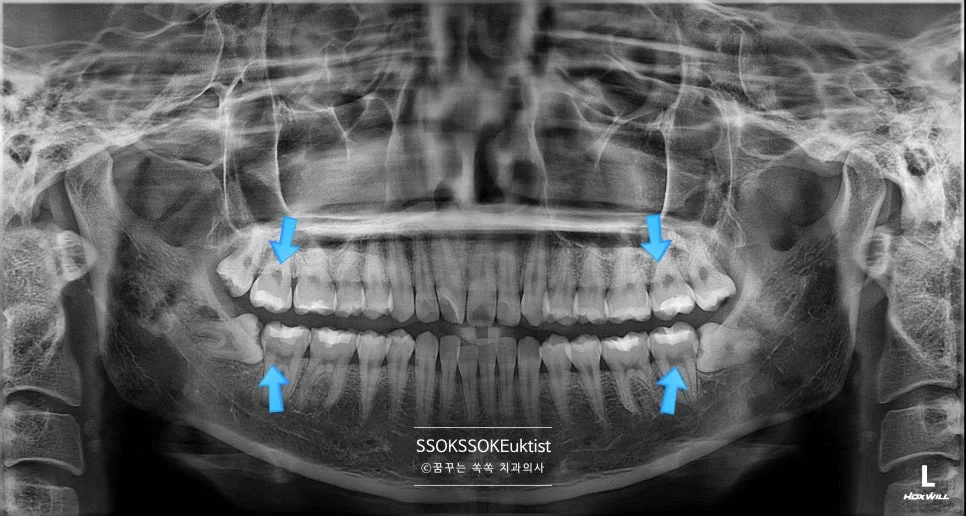

사랑니 4개 위치 파노라마 엑스레이 진단

좋은 진료를 정직하게 | 선한 영향력으로 더 나은 가치를 사랑니 발치 후 식사, 음주, 흡연 언제부터 가능할까? 마곡역 사랑니 최소 통증 해결 TIP | 치과의사 박상억입니다 🙂 안녕하세요^^ 사랑니, 이름만 들어도 이름과 달리 아프고 불편한 무서운 존재로 인식이 되는데요. 이번 포스팅에서는 사랑니를 발치해야 하는 이유와 무섭지 않게 치료받는 방법, 주의 사항까지 자세히 설명드리겠습니다^^ 포스팅 내용만 … 더 읽기

사랑니 4개 발치 전 파노라마 엑스레이 진단 사진

좋은 진료를 정직하게 | 선한 영향력으로 더 나은 가치를 사랑니 4개 한번에 발치, 정말 가능할까? 덜 아프게 뽑는 비결 공개 강서구 마곡 꿈꾸는 쏙쏙 치과의사 박상억입니다. 안녕하세요^^ “하루에 사랑니 4개를 다 뽑으면 너무 아프지 않을까?” “하루에 다 뽑으면 밥은 어떻게 먹죠?” “사랑니 발치 후 술, 담배 가능한가요?” 오늘은 왼쪽 위 사랑니가 붓고 아파서 내원하셨다가, “마취한 … 더 읽기